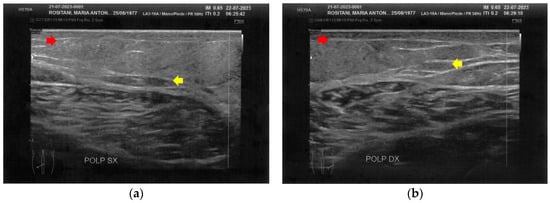

3.1. Basal Imaging Evaluations